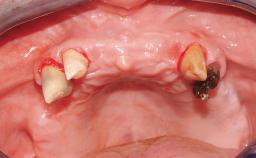

A 35-year-old Caucasian female presenting with advanced periodontal disease involving both the maxillary and the mandibular dentition was referred for evaluation. The patient, a non-smoker in good general health, requested treatment for recurrent periodontal abscesses, tooth mobility, and discomfort during chewing, as well as restoration of her missing teeth with a fixed prosthesis to improve mastication and esthetics. All residual maxillary teeth exhibited plaque deposits, deep pockets, bleeding on probing, and class III mobility and were evaluated as hopeless. All residual mandibular teeth except tooth 37 could be maintained after periodontal therapy.

# of Implants 8

Bone Augmentation Horizontal|Staged|Vertical

Augmentation Materials Autogenous block(s)